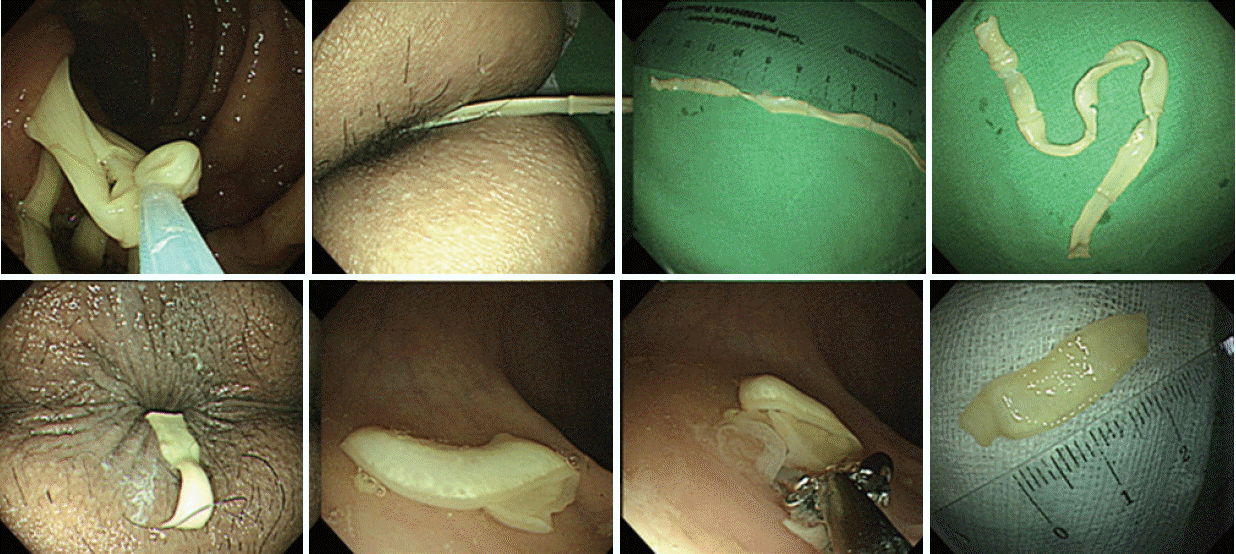

Colonoscopic findings showed a milky whitish to slightly yellowish, long flat tapeworm from the ileum to the ascending colon. The proglottids revealed continuous waving motility, and many uterine branches were seen. The genital pore was located at the lateral end of each proglottid (Fig. 2). Uterine branches were well observed when they were passively adhered on the colonic haustra. At pulling the parasite by endoscopic snare, the proglottids looked like a typical bamboo joint appearance and increased opacity (Fig. 2). After slight pulling of the proglottids, the worm showed active mobility to resist the pulling force and then climbed up to the ileum. Total 12 cm proglottids were removed; the size of each proglottid was about 2.5×0.6 cm. Several pieces of proglottids remained on the rectum revealed wavy widen-and-narrow motility on horizontal plan (Fig. 3).